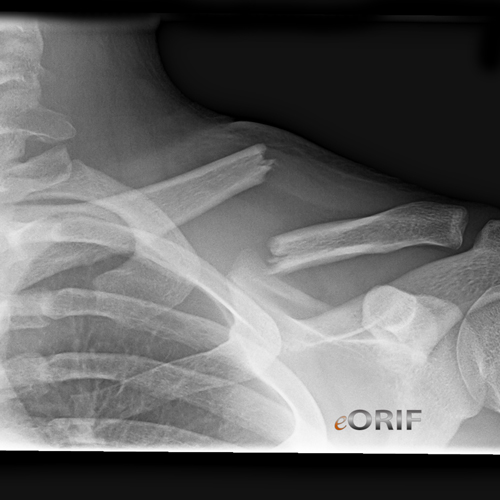

From eorif.com

Clavicle Fracture Malunion S42.009P 733.81 eORIF Pain In Left Clavicle Icd 10 Fracture of unsp part of left clavicle, init for opn fx; This code description may also have includes, excludes,. M25.512 is a billable diagnosis code used to specify pain in left shoulder. Pain quick reference for icd‐10‐cm. Coding of acute or chronic pain in icd‐10‐cm are located under category g89, pain, not elsewhere classified. Open fracture of left clavicle; The. Pain In Left Clavicle Icd 10.